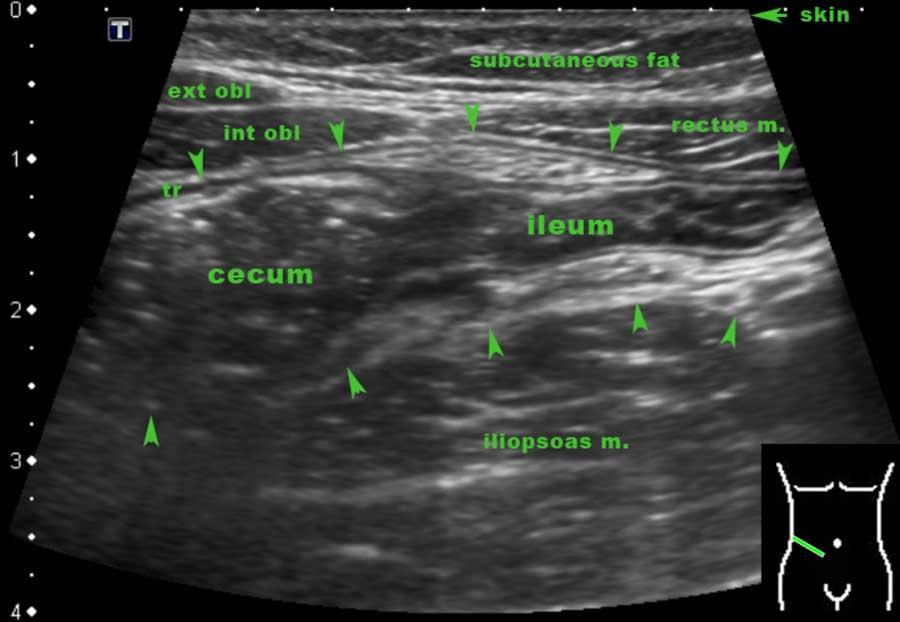

Terminal ileum

Hồi tràng tận thường có thể được xác định riêng biệt do vị trí đặc trưng và đường đi của nó từ vùng chậu hướng về phía rãnh cạnh đại tràng.

Sự đổ vào thực sự của hồi tràng bình thường vào manh tràng chỉ có thể quan sát được ở những bệnh nhân gầy với manh tràng rỗng.

Vị trí của van hồi manh tràng có thể thay đổi rất nhiều, nhưng vị trí trung bình của nó là bên phải rốn.

Thường xuyên hơn, hồi tràng tận có thể được theo dõi cho đến khi nó biến mất vào manh tràng chứa đầy phân.